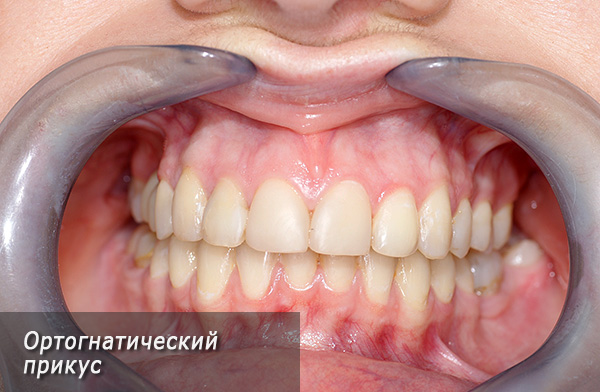

- Morso ortognatico - è considerato il più estetico e più favorevole per mantenere uno stato sano dei tessuti molli della cavità orale e delle articolazioni temporo-mandibolari. Il morso ortognatico ha le seguenti caratteristiche: i denti nella parte laterale sono chiusi secondo la classe I di Engle, vale a dire, il tubercolo anteriore-buccale della "sei" superiore si trova nella fossa inter-tubercolare del 6o dente inferiore. I denti anteriori della mascella superiore si sovrappongono agli incisivi della mascella inferiore di non più di un terzo.Tutti i denti su entrambe le mascelle sono in stretto contatto tra loro. Inoltre, hanno una certa pendenza, garantendo la loro posizione regolare e corretta;

Dopo 3-4 settimane, l'ortodontista, insieme al chirurgo, esamina il paziente e se i medici sono soddisfatti del risultato ottenuto, viene prescritta la rimozione del sistema di staffe.